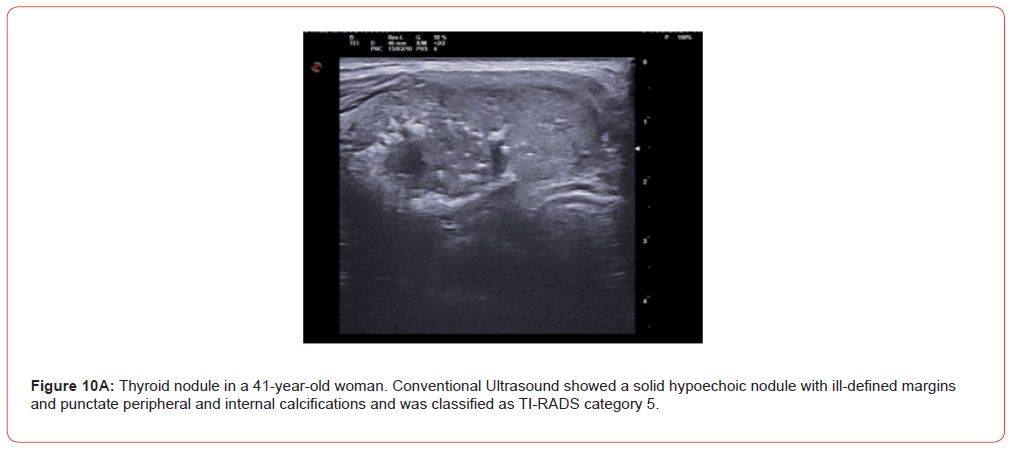

Figure 9 and 10 show representative case of benign and malignant thyroid nodule.